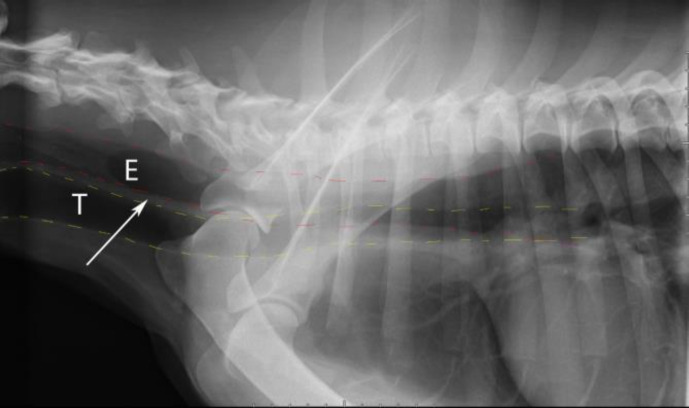

A 2-year-old intact male Asian Shepherd dog was referred with a history of chronic regurgitation along with normal appetite and diagnosis of megaesophagus on plain radiography. Clinical examination revealed normothermia, normocardia, normopnea, low body condition score and poor hair coat. The most important laboratory findings include anemia, azotemia, hyperlipidemia, increased thyroid stimulating hormone, decreased thyroxine and hypocortisolemia, as well as a marked increase in acetylcholine receptor antibody concentration. Based on the results, in addition to primary hypothyroidism and primary hypoadrenocorticism, myasthenia gravis was also diagnosed as an underlying cause of megaesophagus. Following nursing care and preferred treatment of each disease, the megaesophagus was resolved in the next visit. This clinical report describes for the first time, to the authors' knowledge, a dog with a rare type of autoimmune polyglandular syndrome (APS) known in human medicine as a Schmidt's syndrome. We want to emphasize the importance of clinicians' awareness regarding the possibility of APS to identify different diseases caused by it in order to achieve successful treatment.